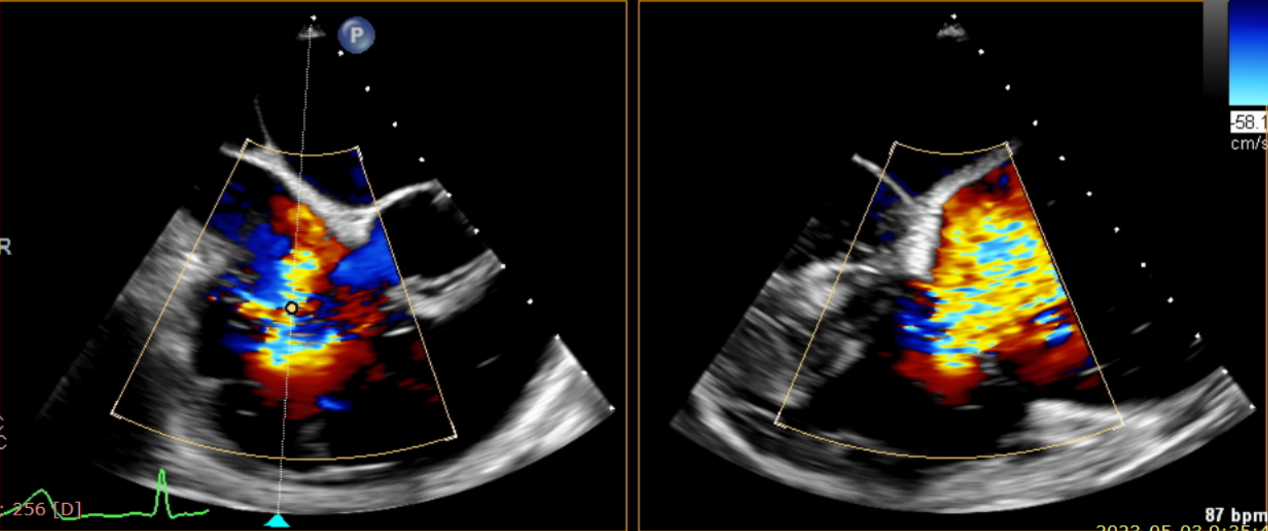

術前超聲提示大量三尖瓣反流

術中輸送器在超聲引導下調整位置